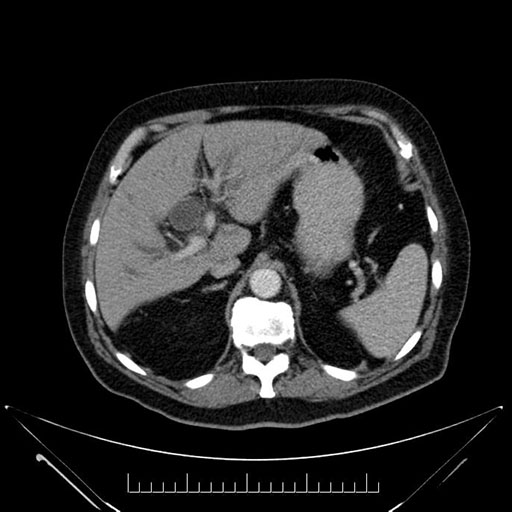

Axial - stented